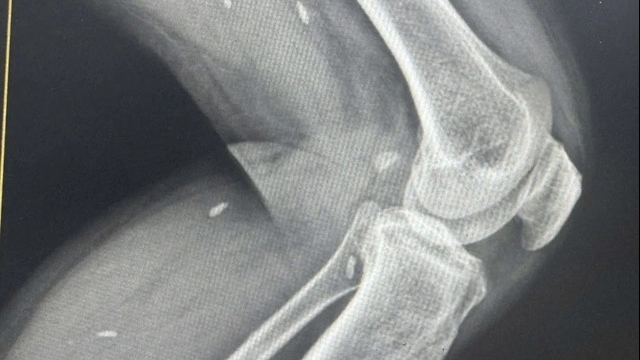

![]() |

| Bác sỹ của Trung tâm Y tế huyện Tam Đảo khám bệnh cho bệnh nhân. |